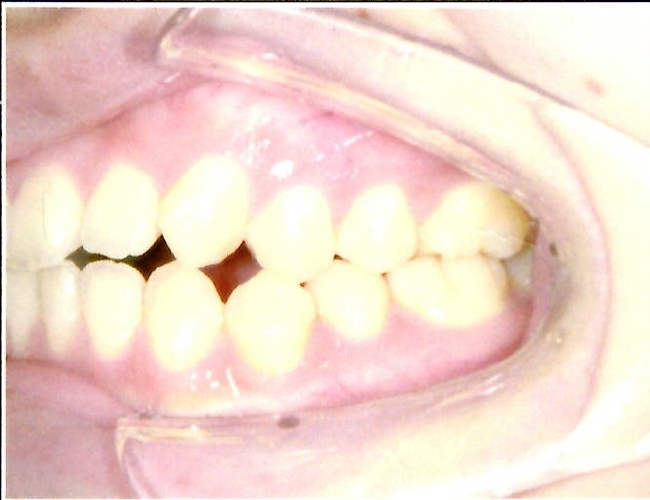

| 主訴・治療前の状態 | 前歯が噛み合っていない状態(開咬傾向)で、犬歯がやや前方に突出しており、見た目にお悩みがありました。 |

| 治療内容 | 上下左右の第一小臼歯(4番)計4本を抜歯し、そのスペースを利用して歯列を整え、前歯の噛み合わせを改善しました。 |

| 治療結果 | 前歯がしっかり噛み合うようになり、見た目も美しく整いました。患者様の満足度が非常に高かった症例です。 |